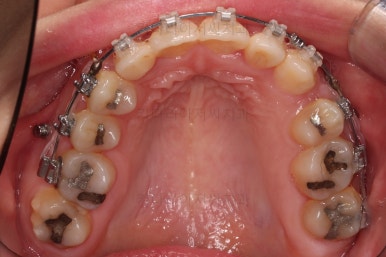

치료 종료 시 입안의 모습입니다.

윗니만 발치를 했지만 교합이 잘 맞고요.

한 쪽 송곳니가 없지만 기능적으로 전혀 문제를 못느끼실 교합을 맞춰놨고요.

위아랫니 가지런해졌고요.

대신 중앙선은 약간 틀어져 있는데요.

한 쪽은 송곳니가 없고 한 쪽은 작은 어금니를 발치했기 때문인데요.

18개월이라는 짧은 기간동안 부정교합, 덧니, 심지어 매복치아까지 개선했는데 양측 치아 사이즈 문제로 생기는 중앙선 정도는 아무 문제가 안되는거죠.